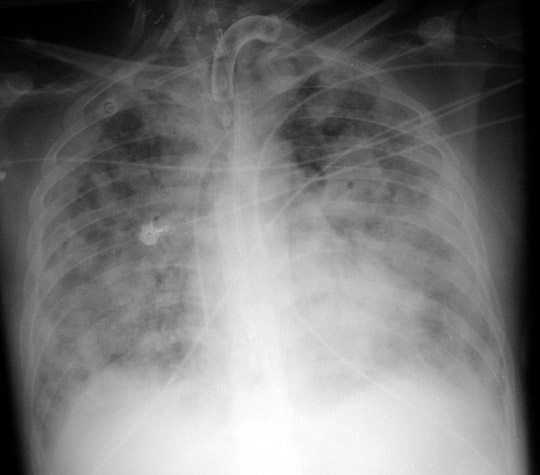

CXR